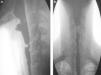

A) Proyección lateral de trago de bario: estenosis en región proximal del esfínter esofágico superior. B) Proyección AP de trago de bario: estenosis medial en región proximal de esfínter esofágico superior, porción proximal a la estenosis se encuentra dilatada, porción inferior a la estenosis con paredes irregulares.

Varón de 30 años de edad con antecedente de epidermólisis bullosa desde la infancia, con varios familiares de primer grado afectados, presenta afección dermatológica generalizada (figs. 1A y 1B), intensificada en los últimos 5 años. Fue referido al servicio de gastroenterología con disfagia orofaríngea de 2 años de evolución y pérdida peso de 10kg relacionada con disminución de la ingesta por alteración de la deglución. Presentaba disfagia a sólidos desde su inicio. Clínicamente se realizó el test de volumen-viscosidad (TVV): los líquidos los toleraba en pequeños volúmenes en el momento de la valoración. Se le realizó endoscopia como parte del protocolo del estudio, encontrando estenosis a los 13cm de la arcada dentaria superior, no franqueable al paso del endoscopio. Trago de bario con estenosis proximal del esfínter esofágico superior (figs. 2A y B); se le propuso como tratamiento, la modificación en cuanto a textura y aporte calórico de los alimentos y gastrostomía percutánea no endoscópica, para realizar dilatación, posteriormente.